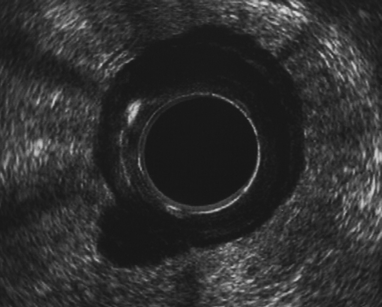

A 71-year-old male patient presented with constipation for one month. No rectal bleeding, pain or tenesmus were associated. Patient did not have a history of contact with or any symptoms of pulmonary tuberculosis. Physical examination was unremarkable, but digital rectal examination revealed hard annular growth about five cm from the anal verge. Colonoscopy showed annular thickening of lower rectum which was covered with a whitish patch. (Figure 1) On suspicision of malignancy, multiple biopsies were taken. Endorectal ultrasonography (B-K Medical HAWK 2102; 2050 anorectal radial probe and a 15 MHz transducer) demonstrated a hypoechoic lesion with pseudopodia. (Figure 2) Computed tomography confirmed a longitudinal circumferential rectal tumor suggestive of malignancy with multiple pelvic lymphadenopathy. (Figure 3) Endoscopic biopsy showed caseous necrosis with inflammatory cells which was suggestive of tuberculosis. (Figure 4) No malignant cells were seen. Chest X-ray showed active pulmonary tuberculosis with positive result for sputum acid fast stain. Anti-HIV ELISA was non-reactive. Serum carcinoembryonic antigen (CEA) was 4 ng/mL. Tissue acid fast stain and tissue culture for tuberculosis were negative. Standard six-month anti-tuberculosis medication was prescribed. The patient responded well to the treatment. His constipation improved. His rectal tumor had receded at the six- month endoscopic follow-up. | ||||||